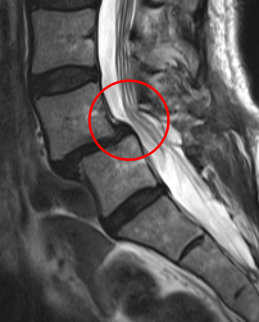

治療後

術後の翌日には痺れが軽減。術後2週間程度で痛みは10から0に、左下肢疼痛は10から1に緩和しました。また術後のMRIでも狭窄症の圧迫がきれいにとれていました。